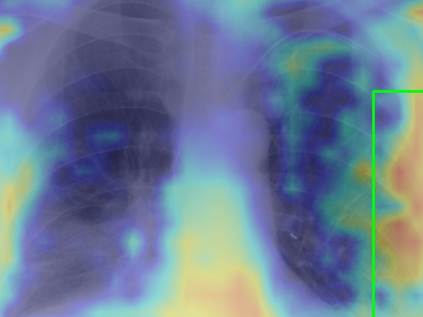

Tuberculosis remains a critical global health issue, particularly in resource-limited and remote areas. Early detection is vital for treatment, yet the lack of skilled radiologists underscores the need for artificial intelligence (AI)-driven screening tools. Developing reliable AI models is challenging due to the necessity for large, high-quality datasets, which are costly to obtain. To tackle this, we propose a teacher--student framework which enhances both disease and symptom detection on chest X-rays by integrating two supervised heads and a self-supervised head. Our model achieves an accuracy of 98.85% for distinguishing between COVID-19, tuberculosis, and normal cases, and a macro-F1 score of 90.09% for multilabel symptom detection, significantly outperforming baselines. The explainability assessments also show the model bases its predictions on relevant anatomical features, demonstrating promise for deployment in clinical screening and triage settings.